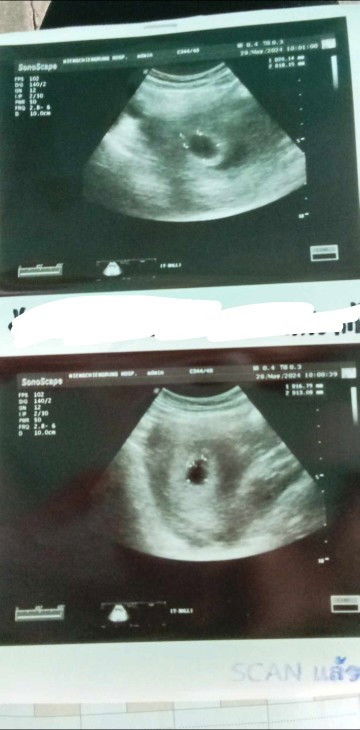

ซาวไม่เจอตัวน้อง

แม่ๆเจอตัวน้องกี่วีคค่ะ วันนี้ไปซาวเจอแต่ถุงตั้งครรภ์ ไม่เจอตัวตน้อง #7week #ขอคำแนะนำกับแม่ๆด้วยนะคะ